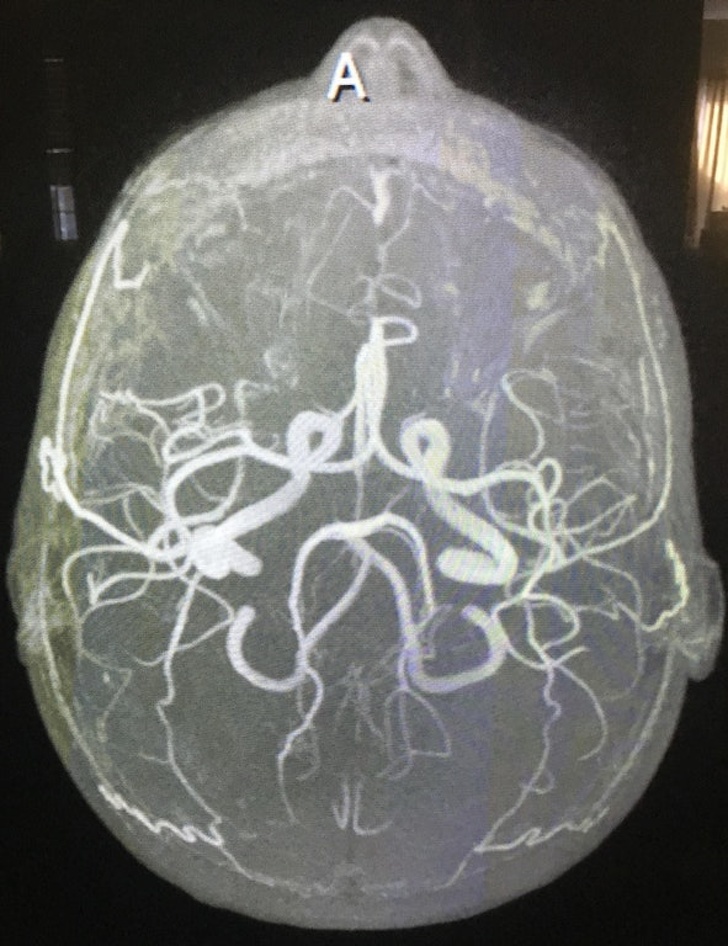

9. Серфінг без хвиль

13. За допомогою МРТ можна побачити артерії мозку